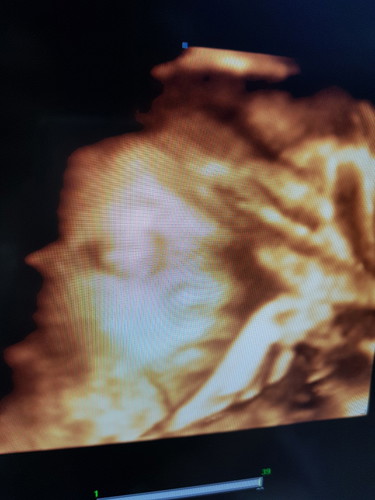

ซาว 4D

ขอสอบถามแม่ๆที่ซาว4d ลูกออกมาเหมือนตอนซาวไหมคะ แม่บ้านนี้ ซาวลูกจมูกใหญ่ ปากใหญ่มากค่ะ ไม่เหมือนพ่อกัยบแม่เท่าไร แอบกังวลค่ะ มีแต่คนบอกลูกเราขี้เหร่

มันซูมเข้าหน้าท้องเราค่ะแม่ เลยทำให้ทุกๆส่วนน้องดูใหญ่ไปหมด แม่อย่าคิดมากนะคะแม่บ้านนี้ก็เป็น หมอบอกปกติค่ะแม่ ตอน24weekค่ะรูปนี้